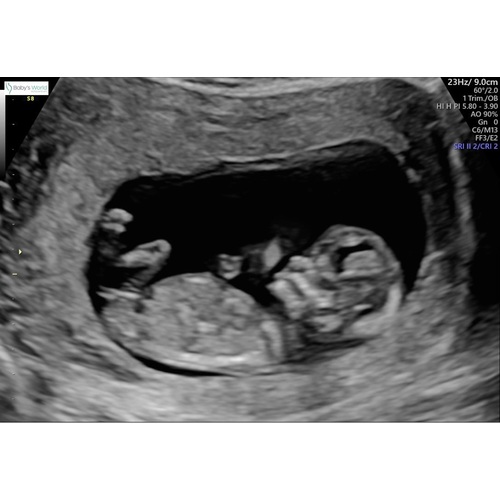

Gister echo gemaakt met 13+3 weken. Wat zal het worden volgens de nub-theorie? Ben zo benieuwd maar zie het zelf niet.